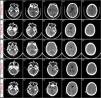

MethodsWe report a patient that presented an abrupt neurological deterioration after cAVM surgical resection. Emergent external ventricular drainage to treat incipient hydrocephalus only partially reverted the patient's deterioration. Consecutive post-surgery CT images revealed fourth ventricle compression secondary to cerebellar swelling that concurred with a new neurological deterioration. Densitometric analysis was performed in these CT images to reveal the nature of these changes as well as their evolution over time.

ResultsImportantly, we demonstrated a dynamic increase in the cerebellum mean density at the interval of Hounsfield values which correspond to hyperemia values. These changes were dynamic, and when hyperemia resolved and cerebellar density returned to basal levels, the fourth ventricle re-expanded and the patient neurologically recovered.

ConclusionsThis study demonstrated the utility of quantitative CT image analysis in the context of hemodynamic alterations following cAVM resection. Densitometric CT analysis demonstrated that hyperemic changes, but not ischemic ones, were time-dependent and were responsible for swelling and hemorrhage that conditioned neurological status and patient's evolution.